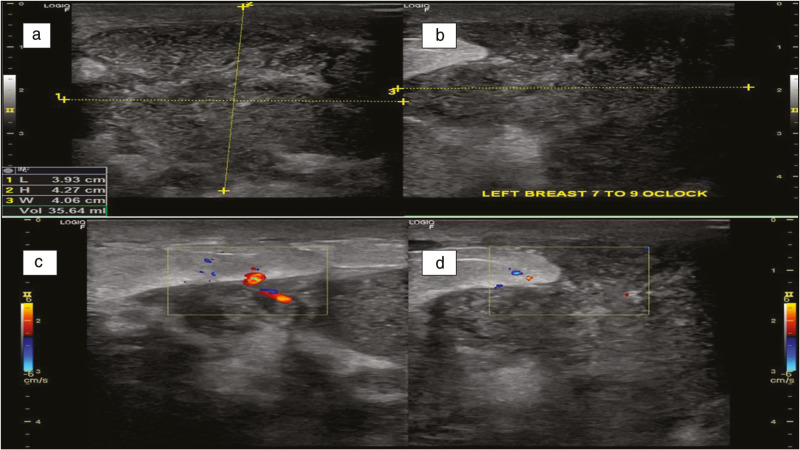

Cystic Neutrophilic Granulomatous Mastitis: A Cytological Evaluation.